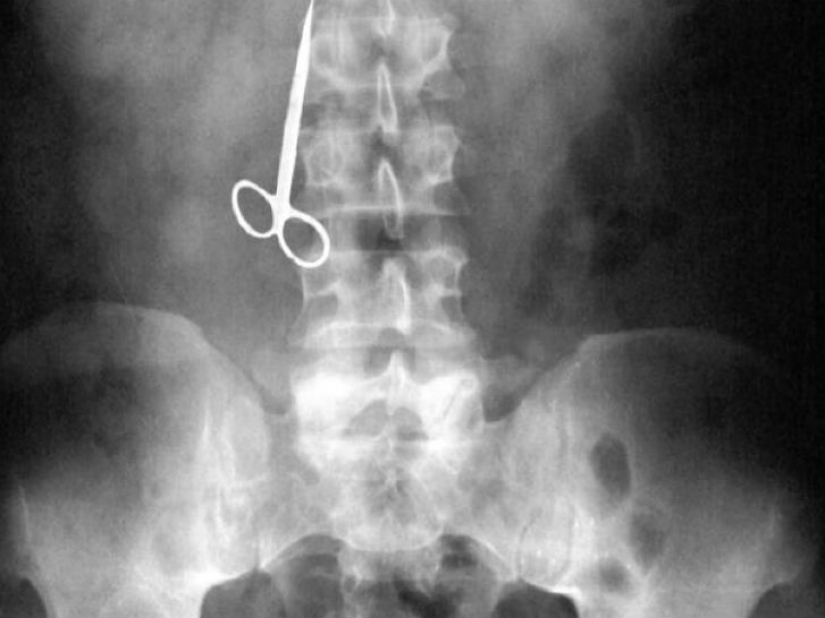

Woman found at home of toothpicks after dinner and decided to use a pair of scissors.